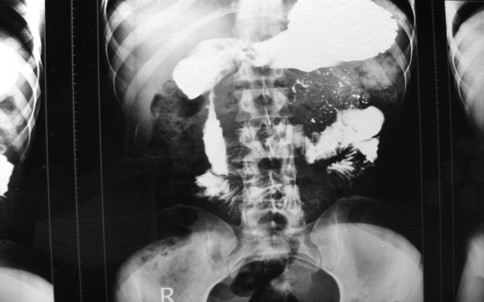

Routine biochemical and hematological investigations were within normal limits. Upper gastrointestinal endoscopy revealed a small benign ulcer at the pyloric area. The first part of the duodenum was injected and was found to be dilated and the second part of the duodenum was narrowed with some extrinsic compression, the scope could not be passed beyond D2 (Figure 2). An abdominal CT revealed a ring of pancreatic tissue encircling the second part of duodenum.

|

Figure 2. Upper gastrointestinal barium study of the pyloroduodenal area revealing narrowing of duodenum at the post bulbar area (Case #2). |